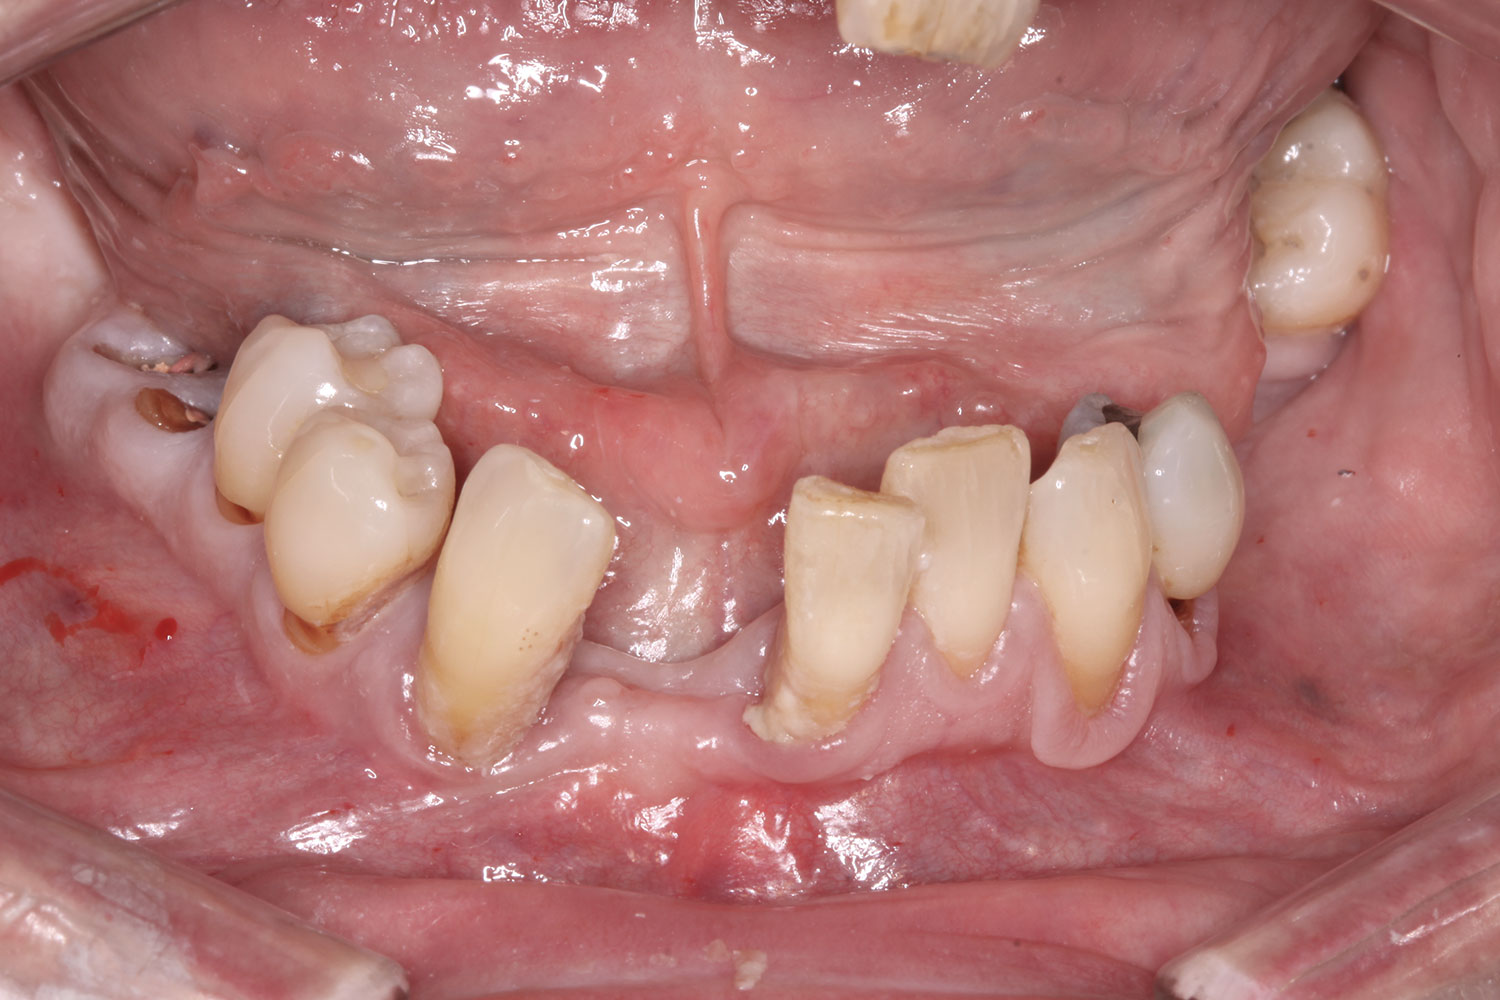

A 36-year-old male patient presented with a highly compromised maxillary dentition comprised of only teeth Nos. 4, 6, 7, 9, 10, 11, and 14 (Figure 1 and Figure 2). This poor condition was the result of only sporadic dental care with extractions and no teeth replacements. Soft tissues had normal contour, and bone profiles were generally sustained and favorable. The patient was excited about having the option to transform his compromised esthetics and function in one visit.

Fig 2. Initial presentation, intraoral view.

Figure 2

Fig 25. Initial clinical presentation, intraoral view.

Figure 25